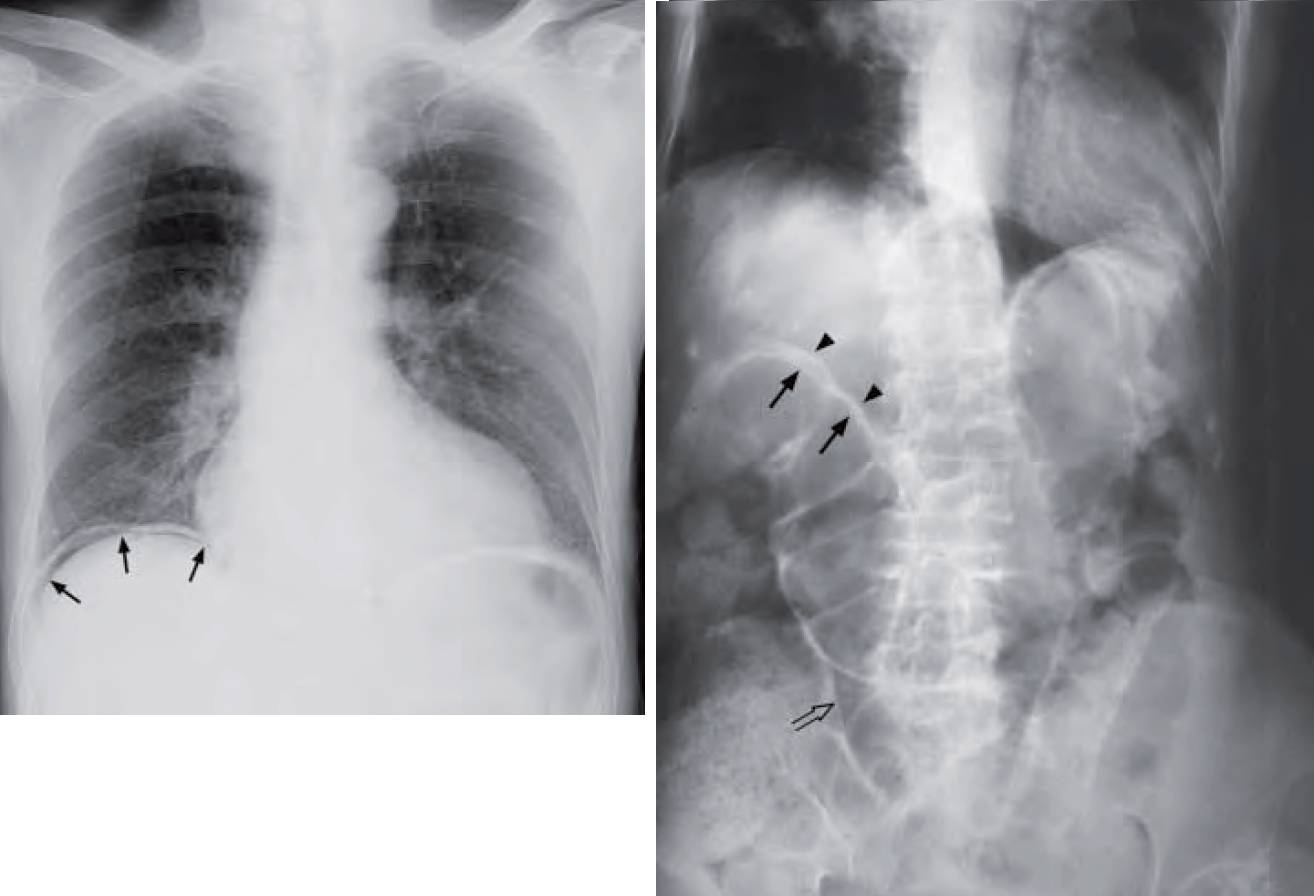

- Left Image: ‘Free gas under diaphragm’ – indicates free peritoneal gas between the dome of the hemidiaphragm and superior surface of liver.

30% of patients with perforated peptic ulcer do not have CXR finding of pneumoperitoneum. An erect CXR is the initial imaging investigation of choice.

The patient should be kept in the erect position for at least 10 minutes before the radiograph is taken to ensure adequate time for free gas to collect in a nondependent portion of peritoneal cavity. If this is not possible, an AXR in the left lateral decubitus position (lying on the side with left side of body dependent) is an alternative. This way, any free gas will float to the nondependent part of the peritoneal cavity (i.e. right side). Pneumoperitoneum, even if substantial, on supine AXR is sometimes difficult to detect.

A CT scan is better at demonstrating the extent of intraperitoneal free gas and detecting small amounts of gas. Note that hepatic interposition of the bowel may mimic free gas under the diaphragm. This is called Chilaiditi’s sign and is seen in asymptomatic patients. When it is associated with symptoms, either intermittent or persistent, it is known as Chilaiditi’s syndrome.